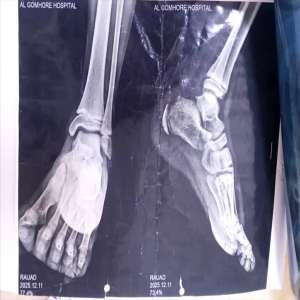

إصابة خطيرة لطفل بعد علوق قدمه في "سيكل" بعدن

تعرّض الطفل رياض، البالغ من العمر 12 عامًا، لحادث مؤلم بعد أن كان يركب دراجة (سيكل)، حيث علِقت قدمه...